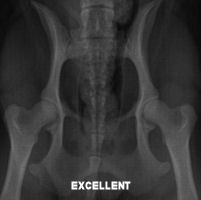

Below are hip x-rays of Cavaliers showing most of the grades of

classification. I don’t have a copy of a Borderline or a Severe.

You can find examples from other breeds online if you are

interested. You can easily see in each x-ray how there is less

and less coverage of the head of the femur (the femoral head—the

round ‘ball’ at the ‘top’ of the leg bone) and the acetabulum

(the ‘cup’ where the femoral head sits) gets more shallow as the

status of the hips declines until they barely overlap at all. In

a severe there is basically no overlapping whatsoever.